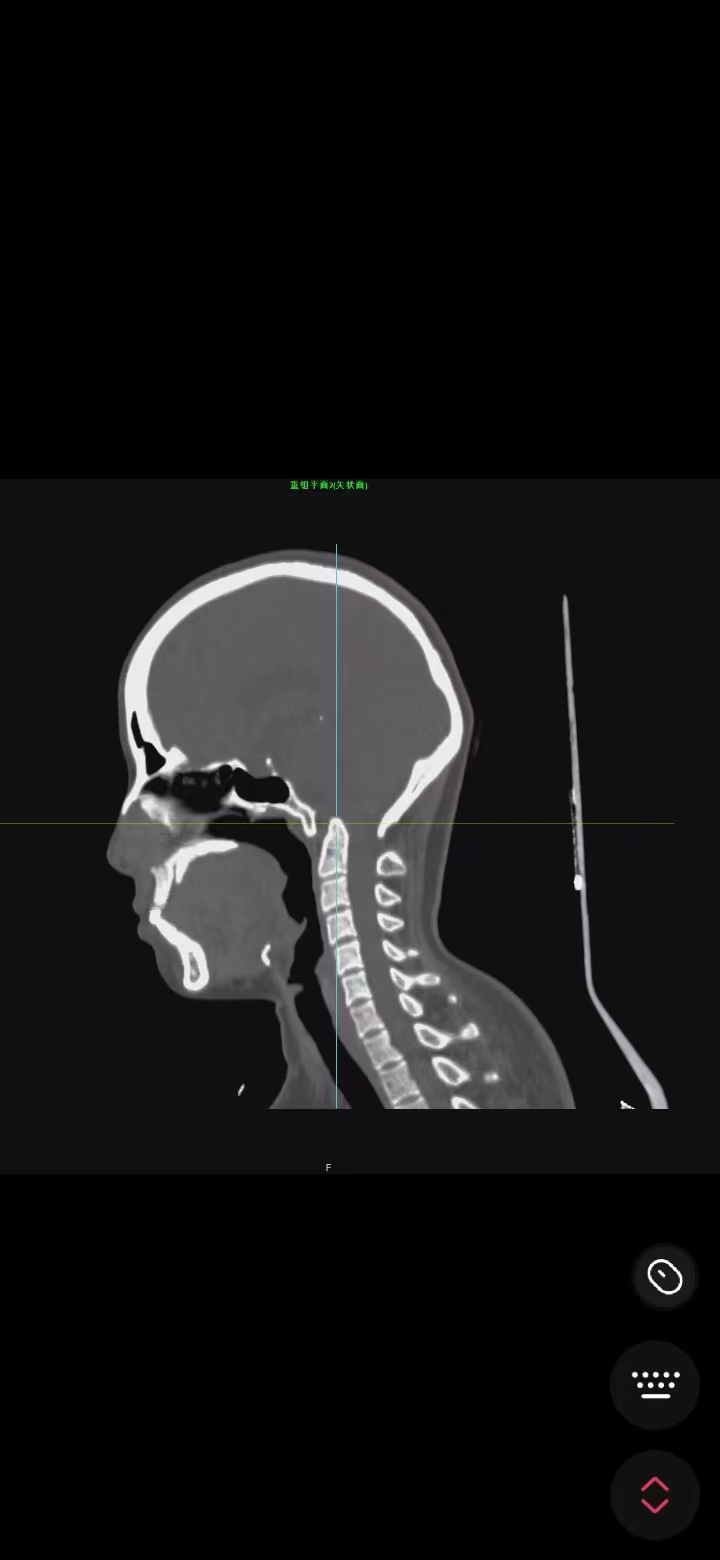

• 诊断:寰枢椎脱位,颅底凹陷

• 影像: